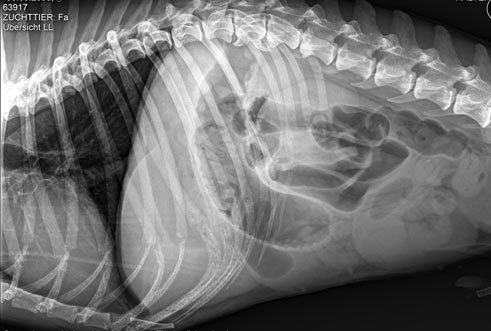

Zu welcher Diagnose gelangen Sie anhand dieses Bildes bei einem Hund mit starken Bauchschmerzen?

Pankreatitis

Paralytischer Ileus

Zwerchfellruptur